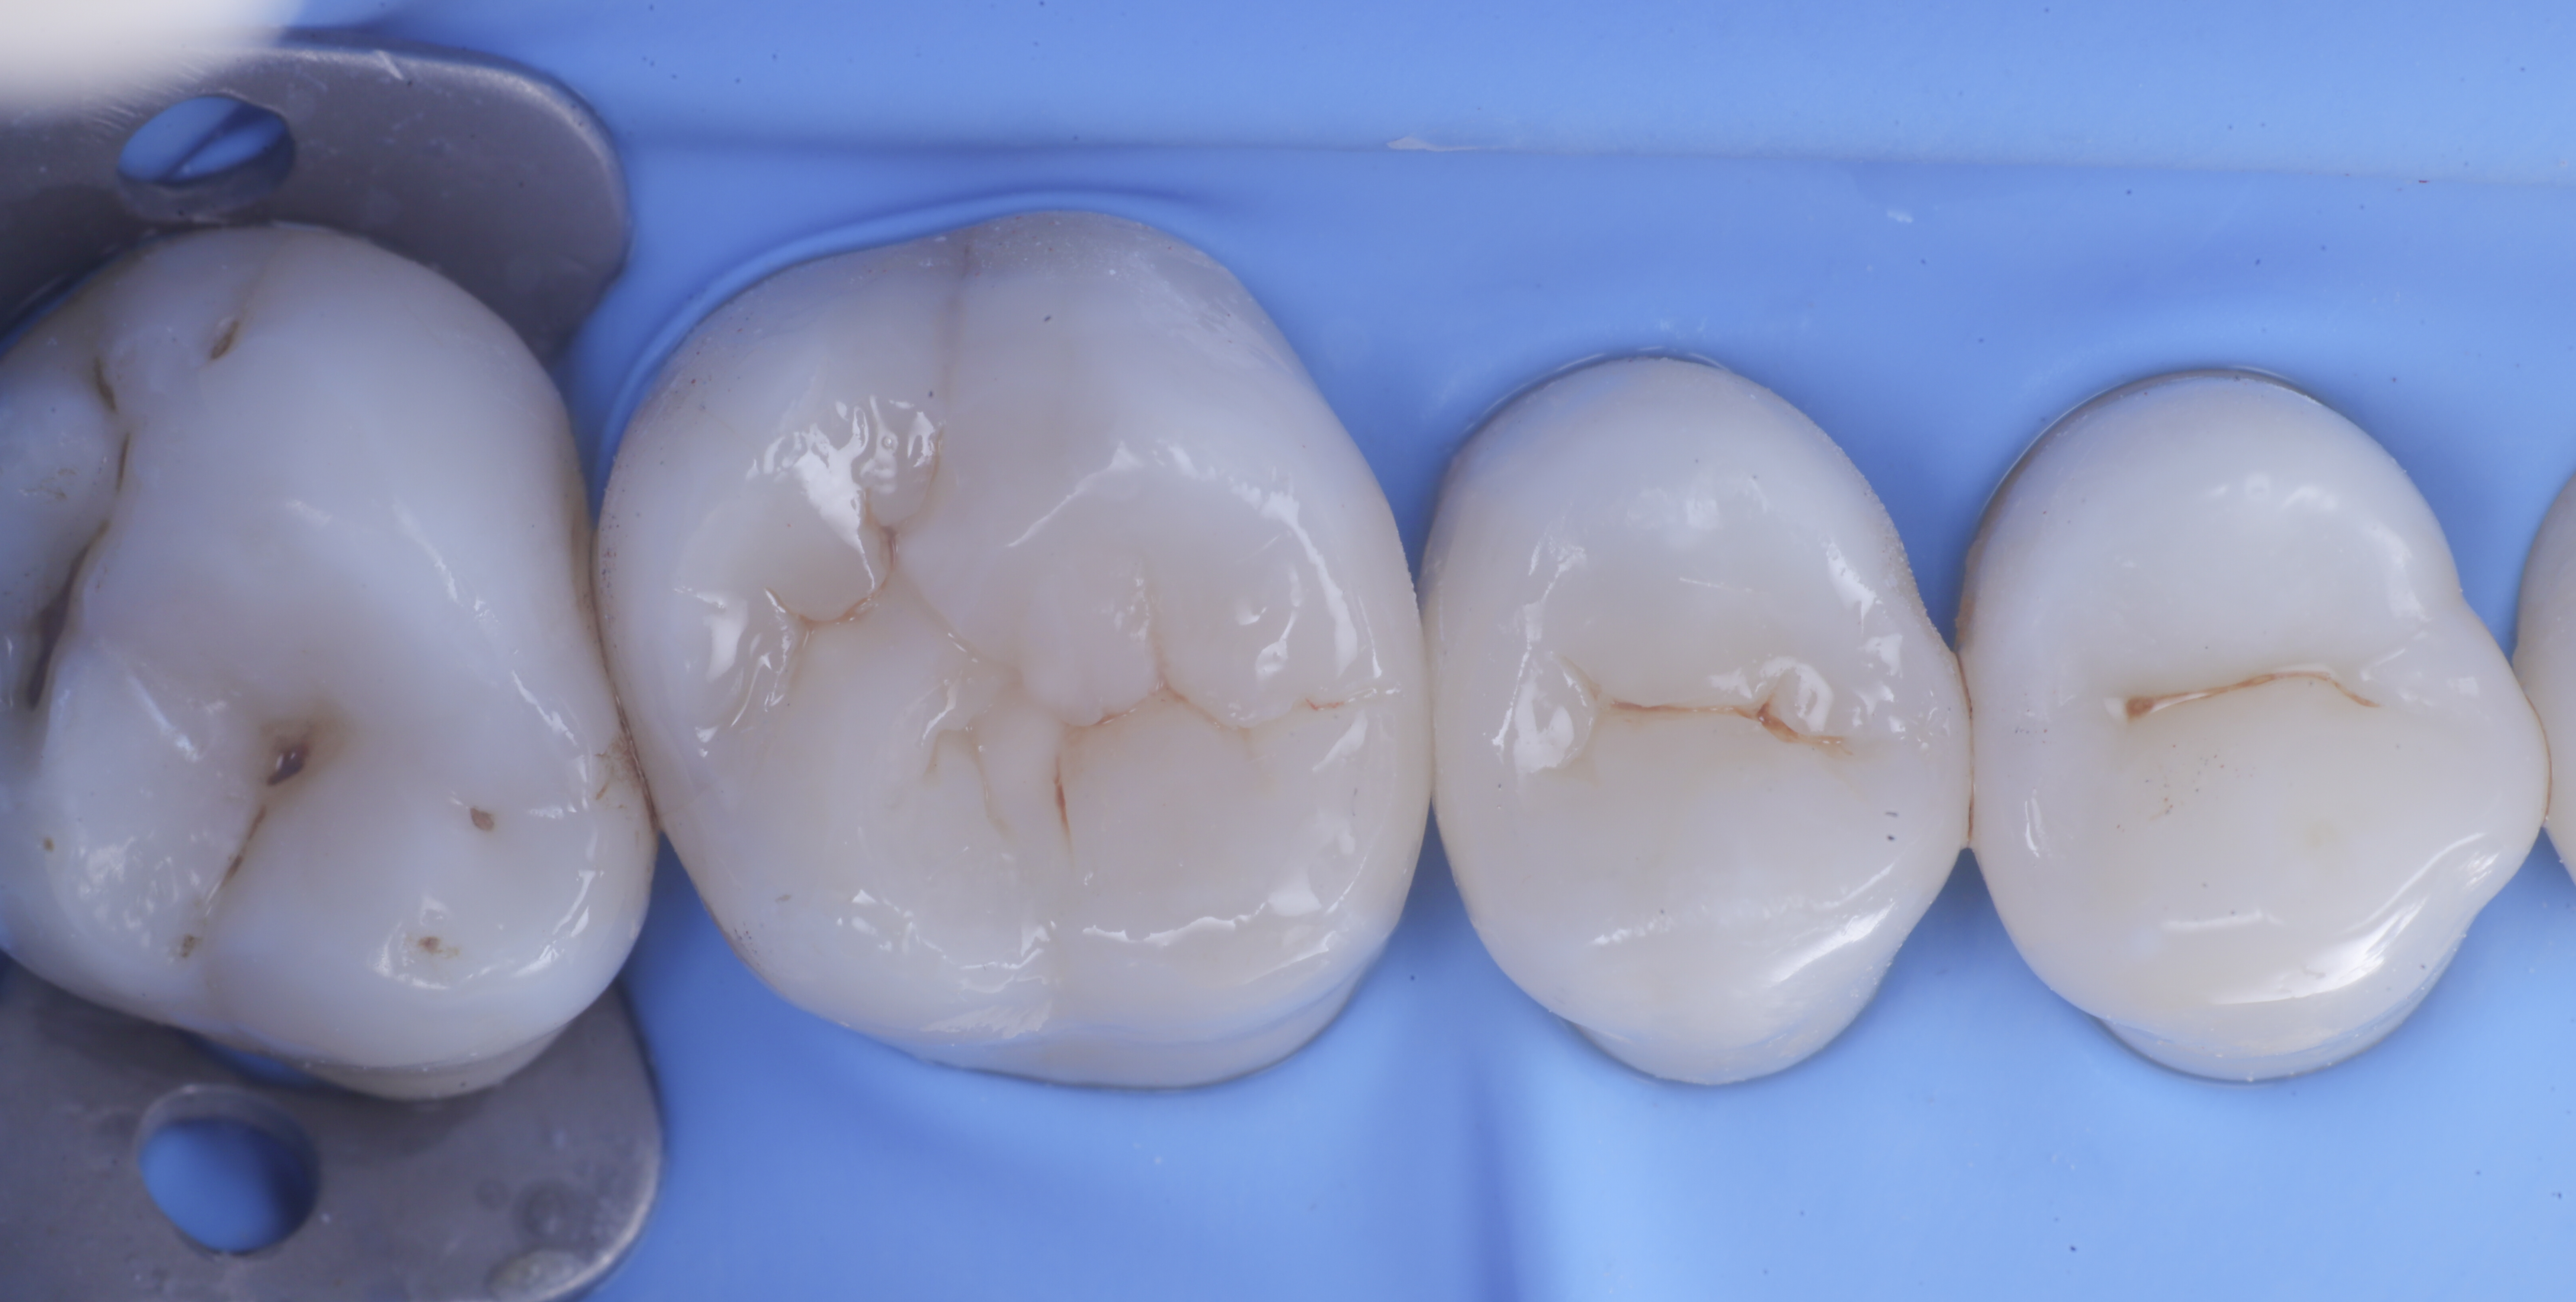

foto 6 Aspetto occlusale delle pareti interprossimali appena create

foto 7 Aspetto vestibolare delle pareti interprossimali appena create

A questo punto si procede con la stratificazione e modellazione di una delle due pareti inter-prossimali e si polimerizza. Si elimina quindi la matrice della parete appena eseguita sposando l’anello che viene immediatamente rialloggiato.

Successivamente, eliminato lo spessore dato dalla seconda matrice, si procede con la creazione della seconda parete.